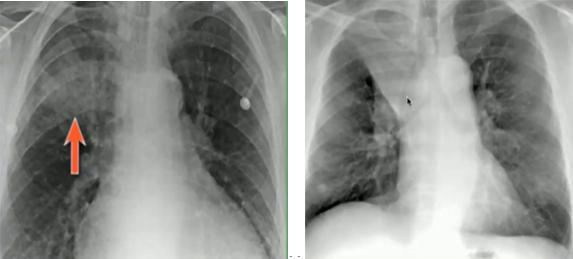

①肺水肿

最初出现弥漫对称的间质性线状阴影,延伸到胸膜边界时表现为横条细线状(KeyleyB征),还可有胸腔积液、上肺血管增粗表现;晚期严重可出现肺实变(从间质累及到肺泡累及),出现蝙蝠翅膀征(严重急性肺水肿时,出现沿肺门翅膀样阴影)。

心源性肺水肿可有明显的心界增大。

图18.线状间质阴影(左);Keyley B征(右)

图19.心源性(左)/非心源性(右)肺水肿

图20.心源性肺水肿:心影增大(绿)、线状间质阴影(蓝)、胸膜增厚(红,卧位时胸腔积液表现)②气胸、纵隔积气、心包积气鉴别